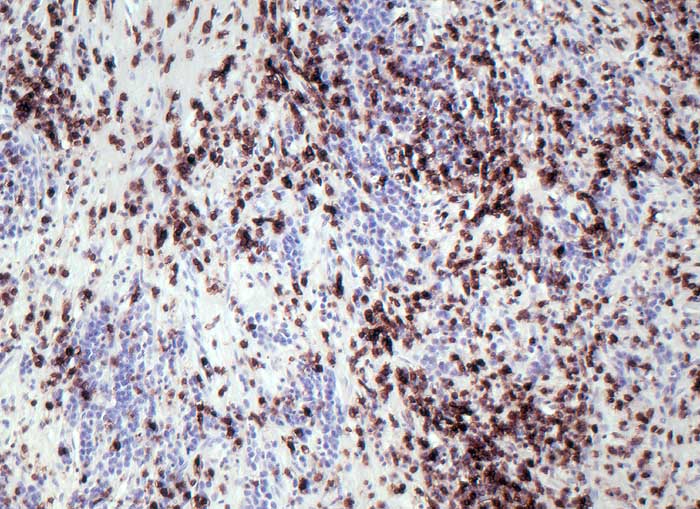

CD45 (leucocyte common antigen, LCA)

- Anfärbung:

- Zellmembran

- Fast alle haematolymphoiden Zellen sind positiv: T-Lymphozyten, B-Lymphozyten, Granulozyten, Monozyten, Makrophagen.

- 93-99% aller Lymphome sind positiv. Einzelne high grade Lymphome sind CD45 negativ und CD20 positiv.